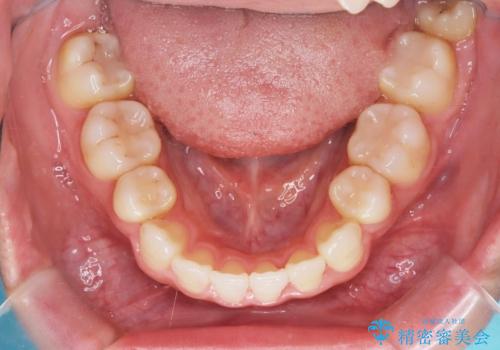

- 治療計画

上下左右の第一小臼歯を抜歯し、クリアブラケット(白い装置)とメタルワイヤーを使用して矯正を開始。初期には犬歯のアーチ内への整列を優先し、中盤からは前歯と奥歯の咬合関係の調整を進めました。審美性に優れた装置を使用したことで、治療中も目立ちにくく、見た目へのストレスが少ない点も評価されています。全体の治療は1年半で完了し、見た目・噛み合わせともに大きく改善。患者本人も「短期間でここまで変わるとは思わなかった」と満足されていました。